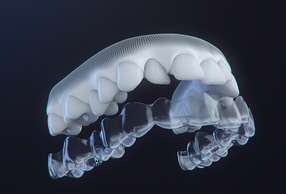

Se oggi dovessi diventare il mio paziente (e l'ho fatto!), sceglierei un approccio digitale, integrato e guidato da una pianificazione 3D. Non per moda, ma per coerenza clinica. Gli strumenti odierni infatti ci consentono di prevedere, simulare e controllare il movimento dentale con un livello di precisione impensabile fino a pochi anni fa. Gli allineatori, inseriti in un protocollo biomeccanico corretto, permettono di coniugare estetica, comfort e controllo.

Direi tre aspetti fondamentali: predicibilità, personalizzazione e comunicazione. La predicibilità deriva dalla possibilità di visualizzare in anticipo gli obiettivi e di programmare ogni fase del trattamento. La personalizzazione consente di adattare la biomeccanica al singolo paziente, evitando protocolli standardizzati. Infine, la comunicazione: mostrare al paziente il risultato atteso migliora l’adesione e la consapevolezza terapeutica. Oggi il paziente è parte attiva del percorso, non più semplice spettatore.

3D Face Scan si basa su una tecnologia avanzata che permette di generare un modello tridimensionale del volto del paziente, mostrando il sorriso da diverse prospettive e in modalità dinamica. Rappresenta uno strumento di supporto alla pianificazione del trattamento, pensato per migliorare il dialogo clinico e la partecipazione attiva del paziente.

Perfetta integrazione con il software ClinCheck®: animazioni, livelli di opacità regolabili e compatibilità con CBCT per una pianificazione più completa e accurata.